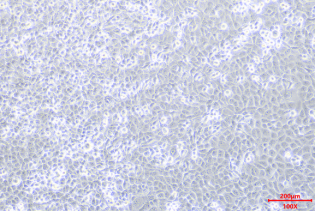

• 形态特性:上皮样细胞

• 生长特性:贴壁生长